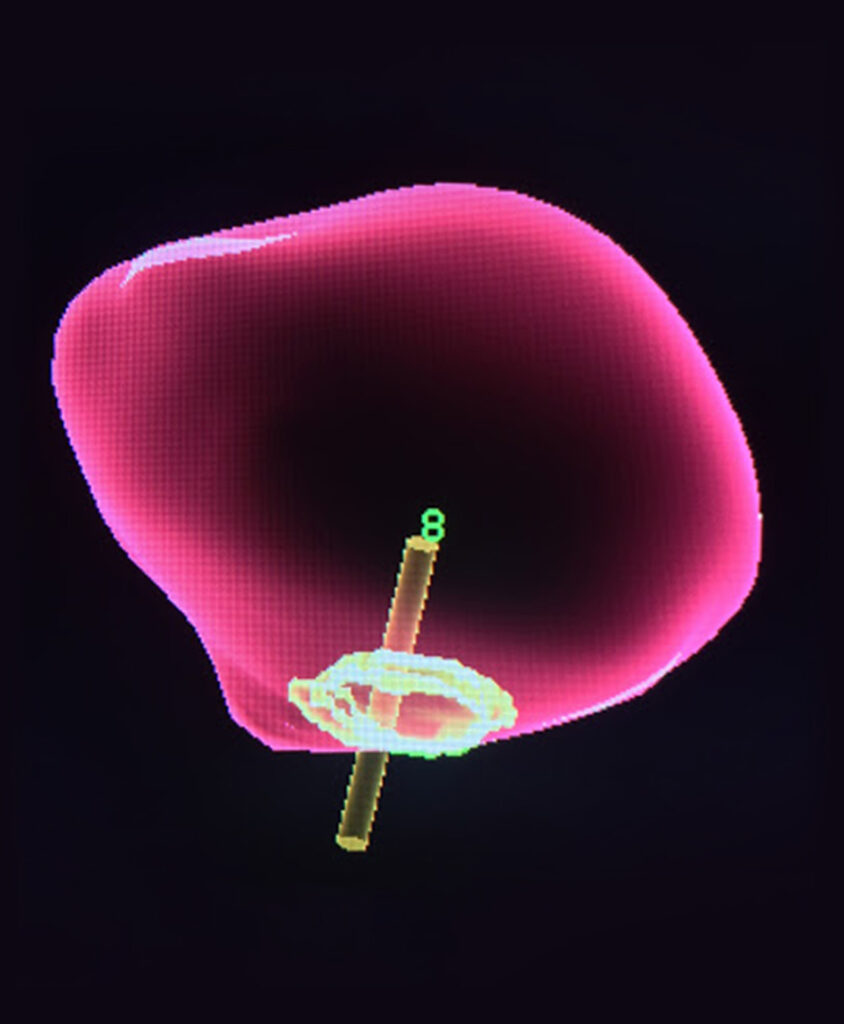

A state-of-the-art approach If prostate cancer is suspected, a biopsy may be required. With the assistance of a high-resolution prostate scan, a more refined, targeted biopsy is performed. At Insite, we use Dynacad software to fuse MRI and ultrasound images together to target potential prostate cancers in real time. The result is a highly-accurate targeting system that demonstrates the precise location of a possible cancer so that doctors can see what was, only a few years ago, often invisible. Our doctors were some of the earliest adopters of this technology and, as such, have acquired a level of experience with it that is exceedingly rare.

- Facilitates more accurate targeting of cancer lesions in a biopsy

- Can help determine the stage of cancer to guide treatment options

- The result is a highly accurate targeting system that demonstrates the precise location of a possible cancer so that doctors can see what was, only a few years ago, often invisible.